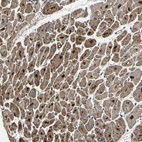

Immunohistochemical staining of human testis shows moderate granular cytoplasmic positivity in cells in seminiferous ducts and leydig cells.